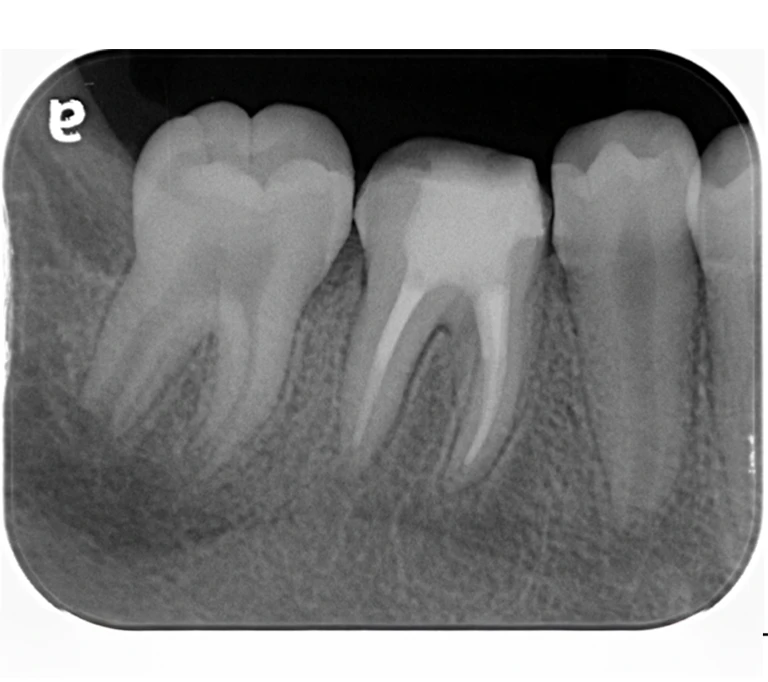

case 4.

治療前

治療後

| 主訴 | 右下奥歯が痛い。 他院で『膿の袋が大きいため抜歯』と言われセカンドオピニオン希望でご来院。 |

|---|---|

| 治療期間 | 約半年(6か月) |

| 治療費 | 約5万円 |

| 治療内容 | ラバーダム、マイクロスコープ下にて根管治療を実施し、歯根端切除を行う。歯茎の腫れは消失し違和感や痛みも消失した。 |

| 治療のリスク | マイクロスコープやCTを使用し、可能な限り精密な根管治療を行っていますが、歯根の形態や病変の大きさ、過去の治療履歴などにより、治癒が得られない場合があります。 また、治療後に再感染や歯根破折が生じることもあり、その場合は再治療や抜歯が必要となることがあります。 治療結果には個人差があり、すべての症例で同様の経過を保証するものではありません。 |